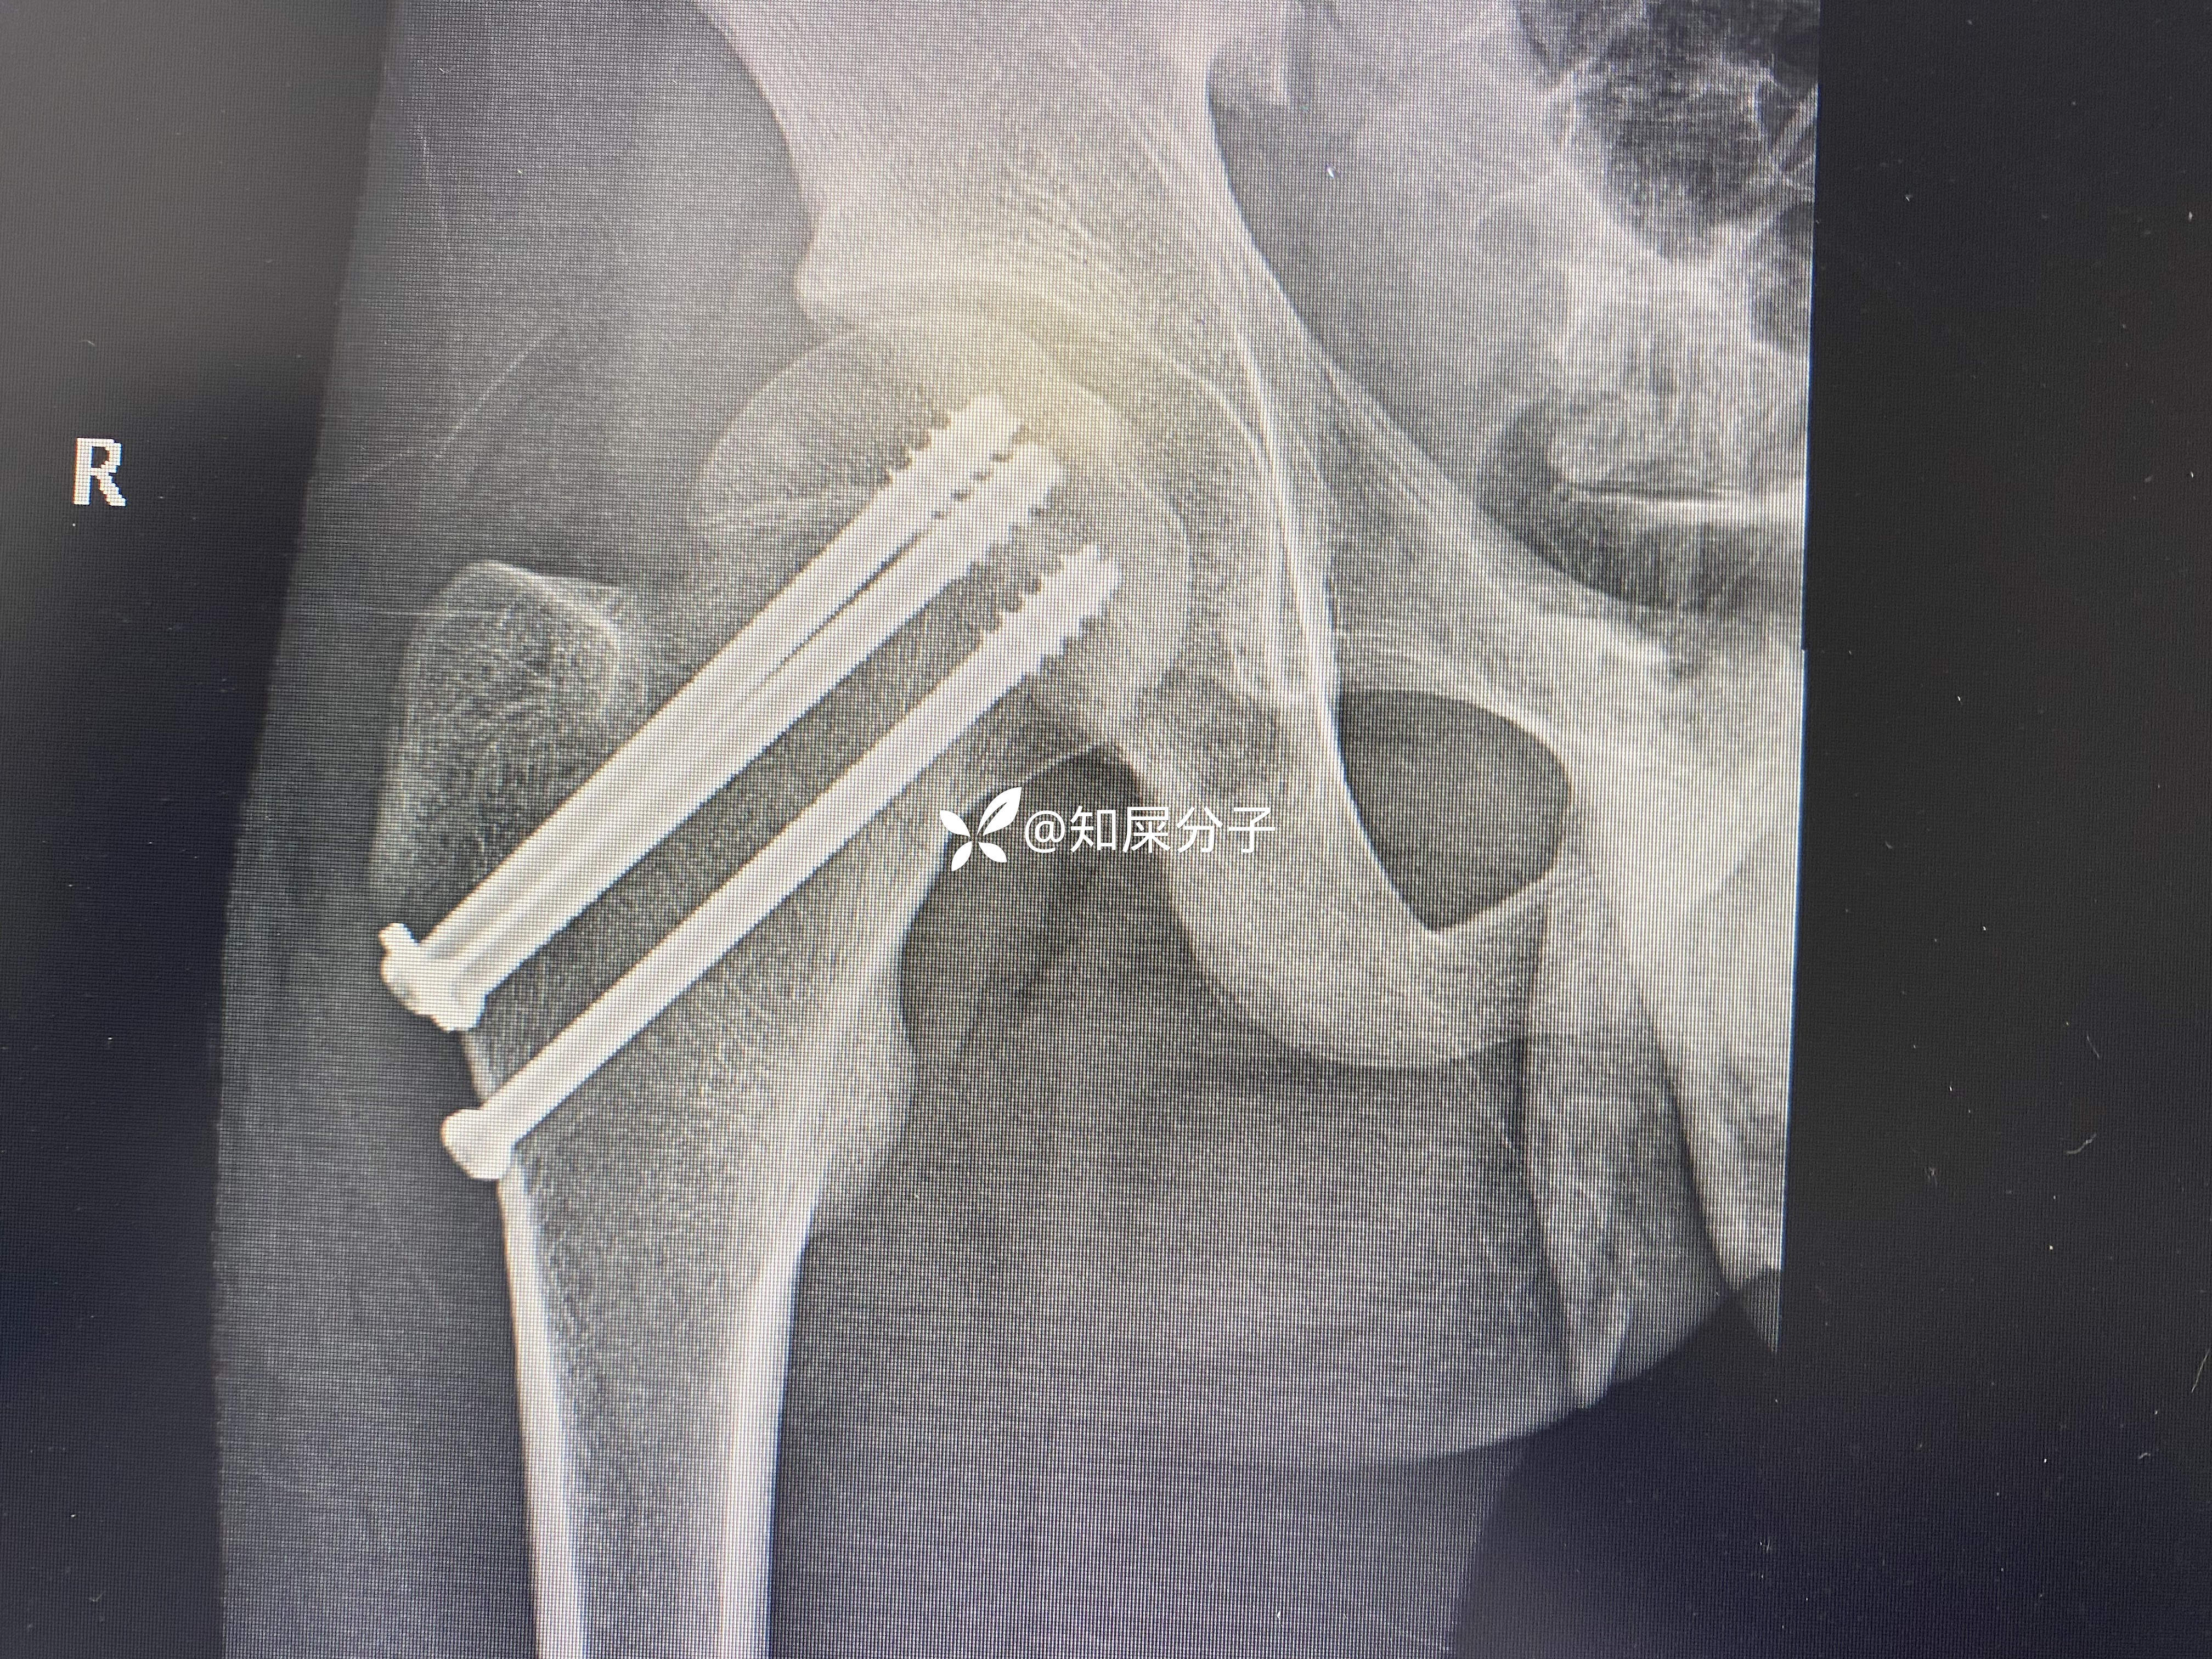

入院后完善检查24小时内完成手术

术后如下